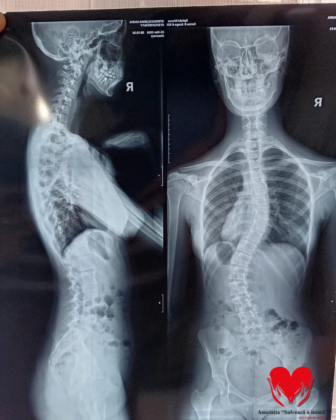

Erika Maria Stingaciu, o adolescentă de 15 ani, duce o luptă grea cu o afecțiune severă – scolioză dorsolombară progresivă, care îi afectează zilnic postura, sănătatea și viața.

Totul a început în 2024, când un control medical aparent banal a scos la iveală o problemă serioasă. De atunci, Erika:

Cu toate acestea, boala a continuat să evolueze.

În februarie 2026, medicii au confirmat că situația s-a agravat și că singura soluție este intervenția chirurgicală.